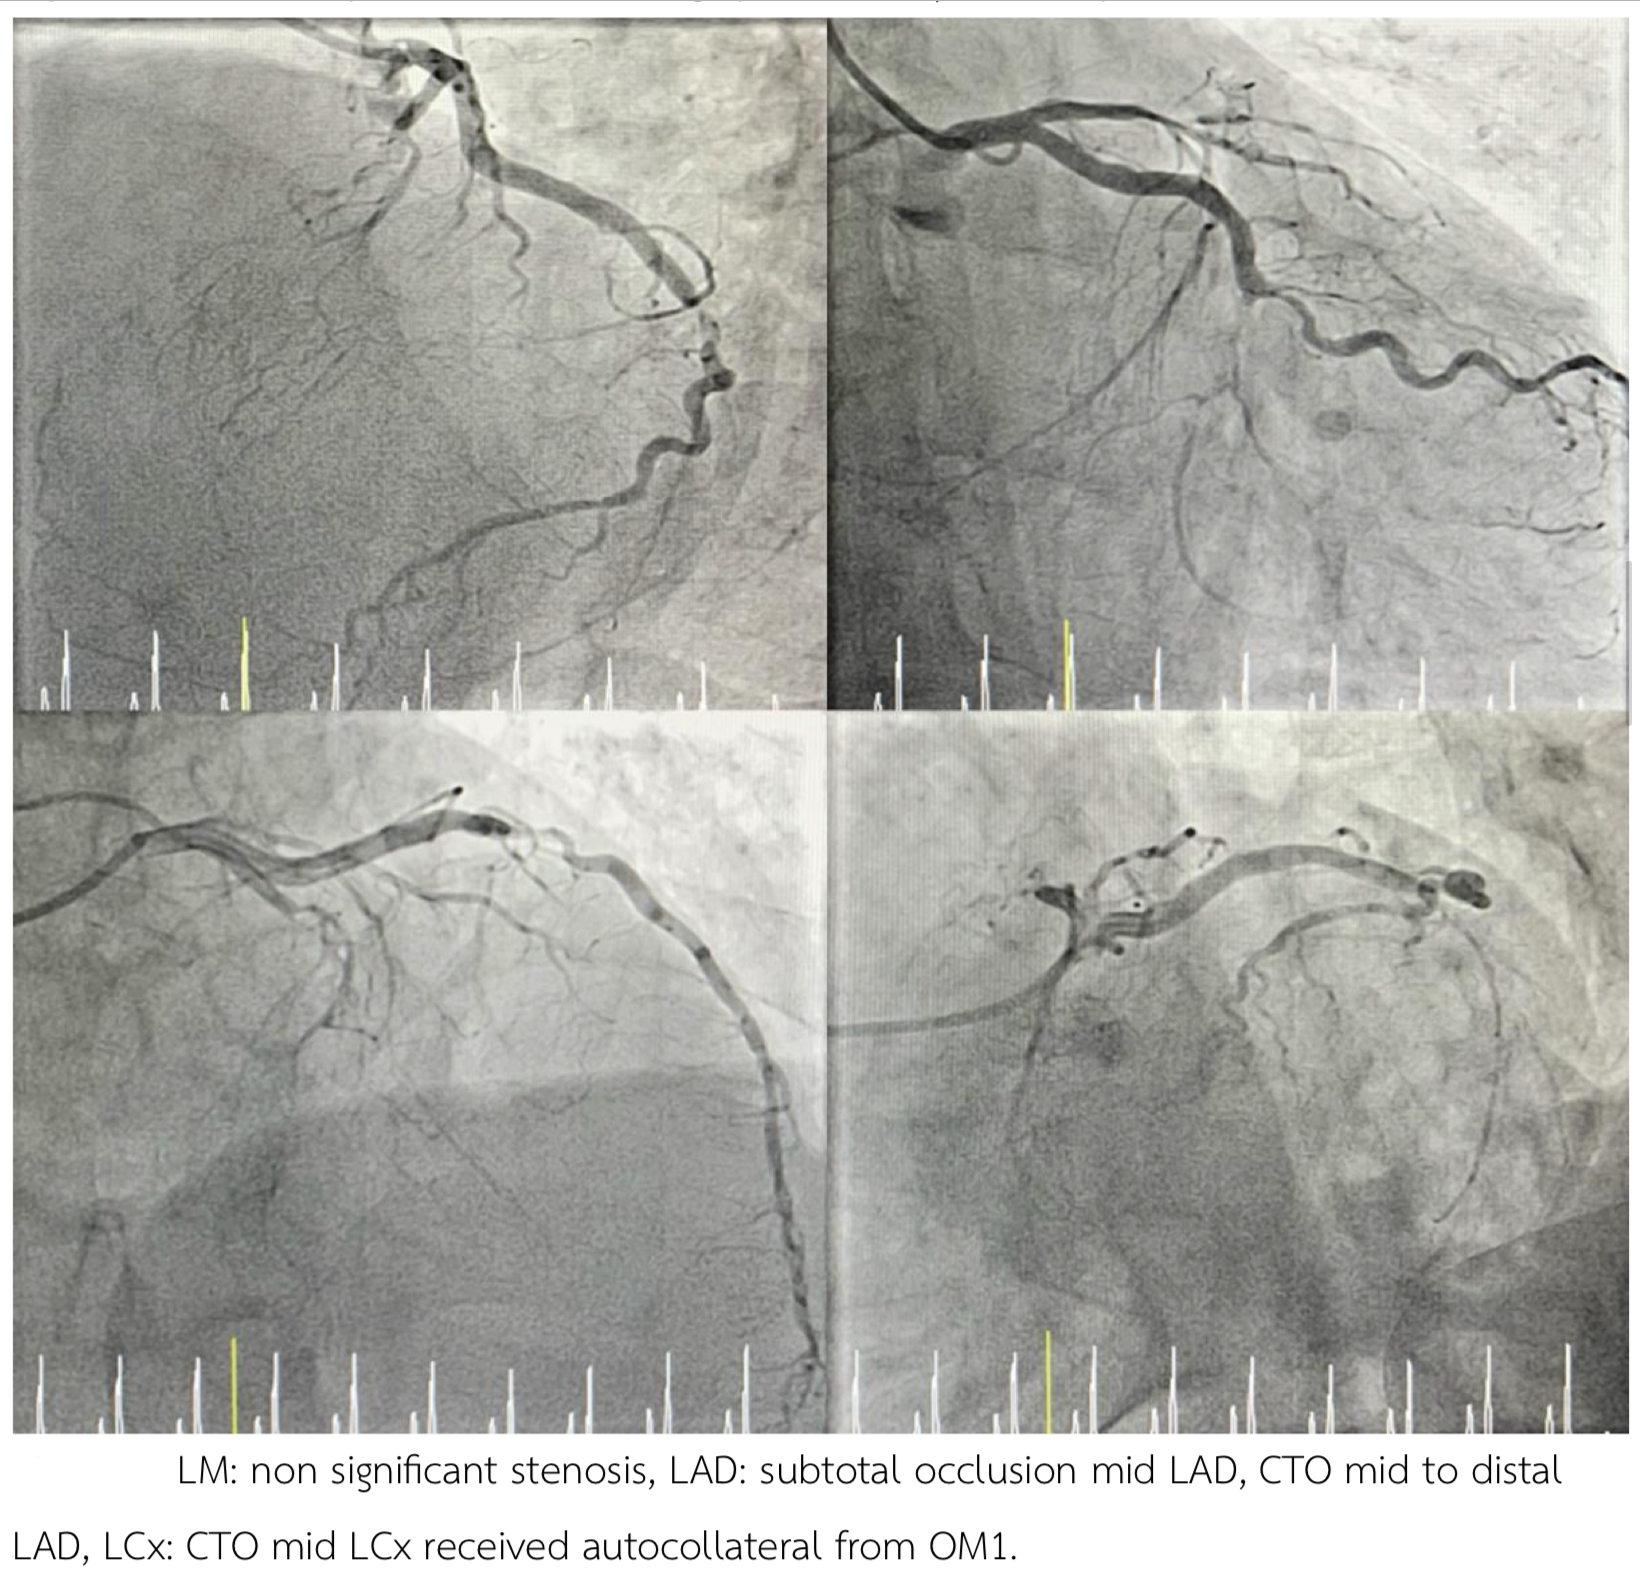

- LM: non significant stenosis - LAD: Subtotal occlusion mid-LAD, CTO m-dLAD. - LCx: CTO mLCx with collateral from OM1. - RCA: Total occlusion pRCA with collateral from LCA.